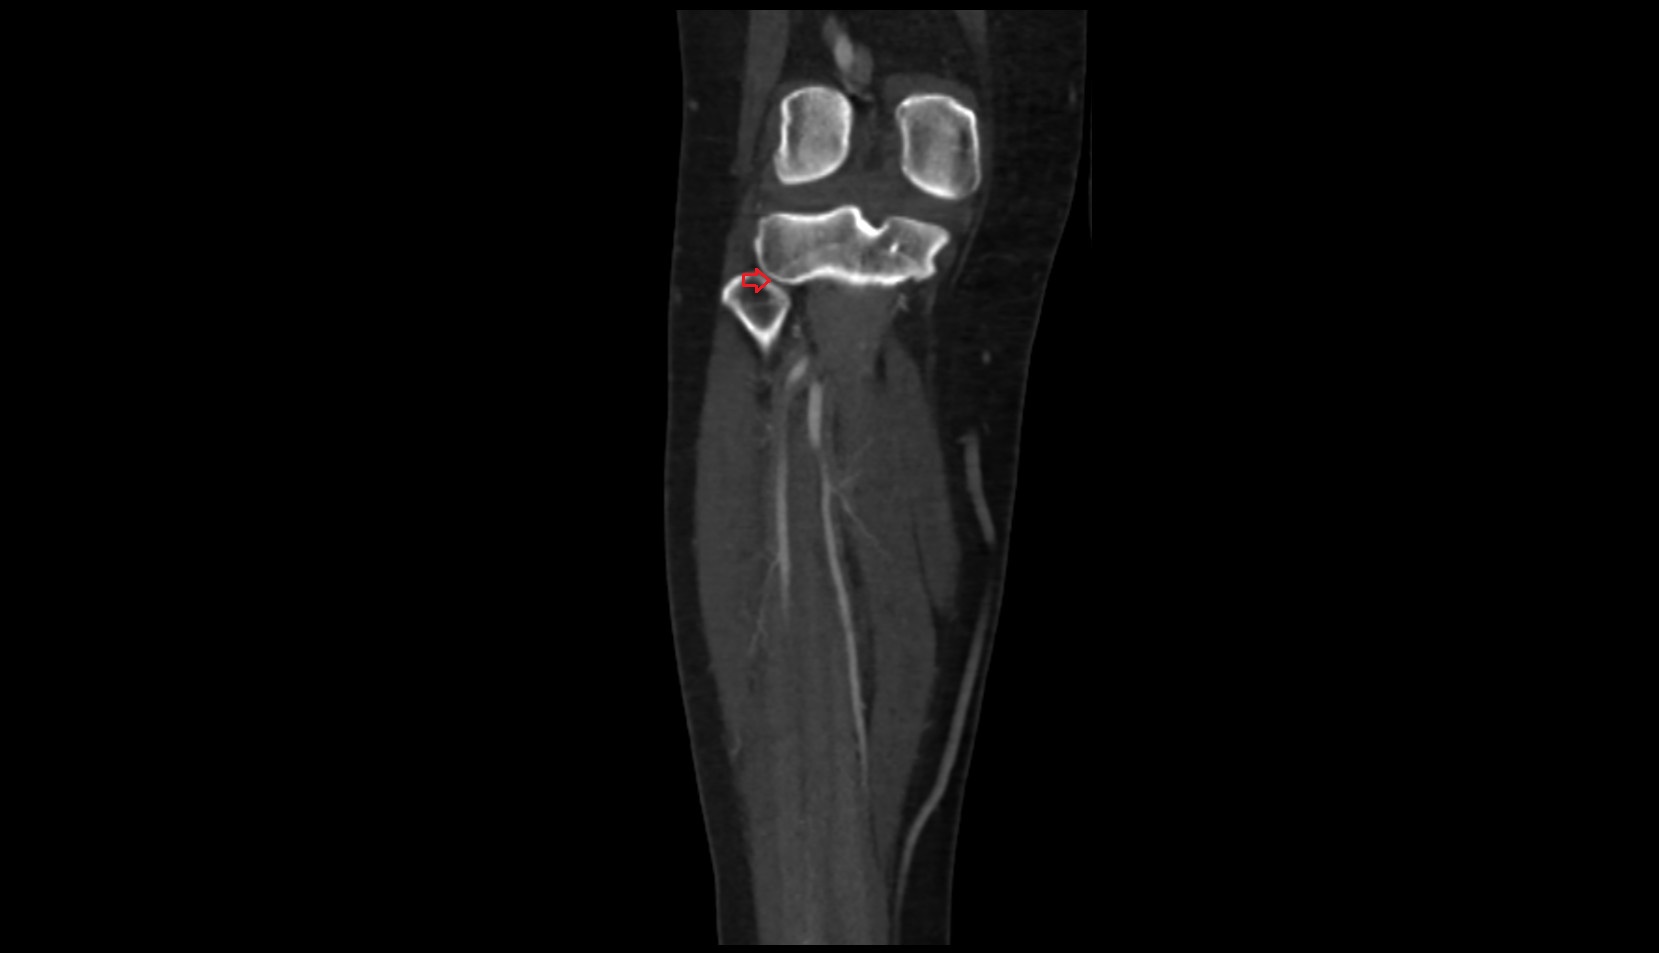

- Elbow joint

- Radius

- Ulna

- Head of radius

- Olecranon